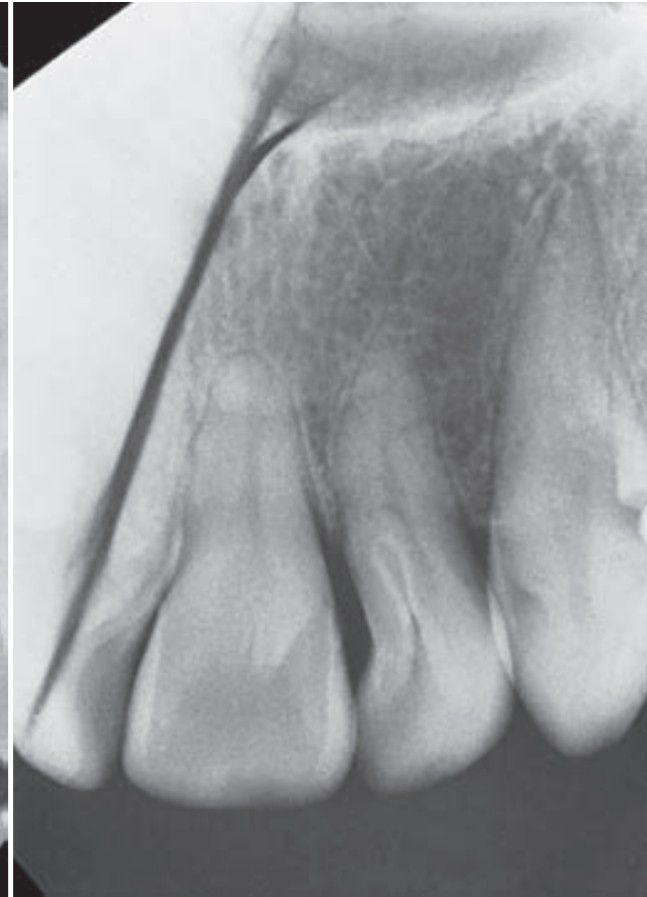

Dens invaginatus

Also known as dens in dente or tooth within a tooth, dens invaginatus is an uncommon tooth anomaly that represents an exaggeration or accentuation of the lingual pit